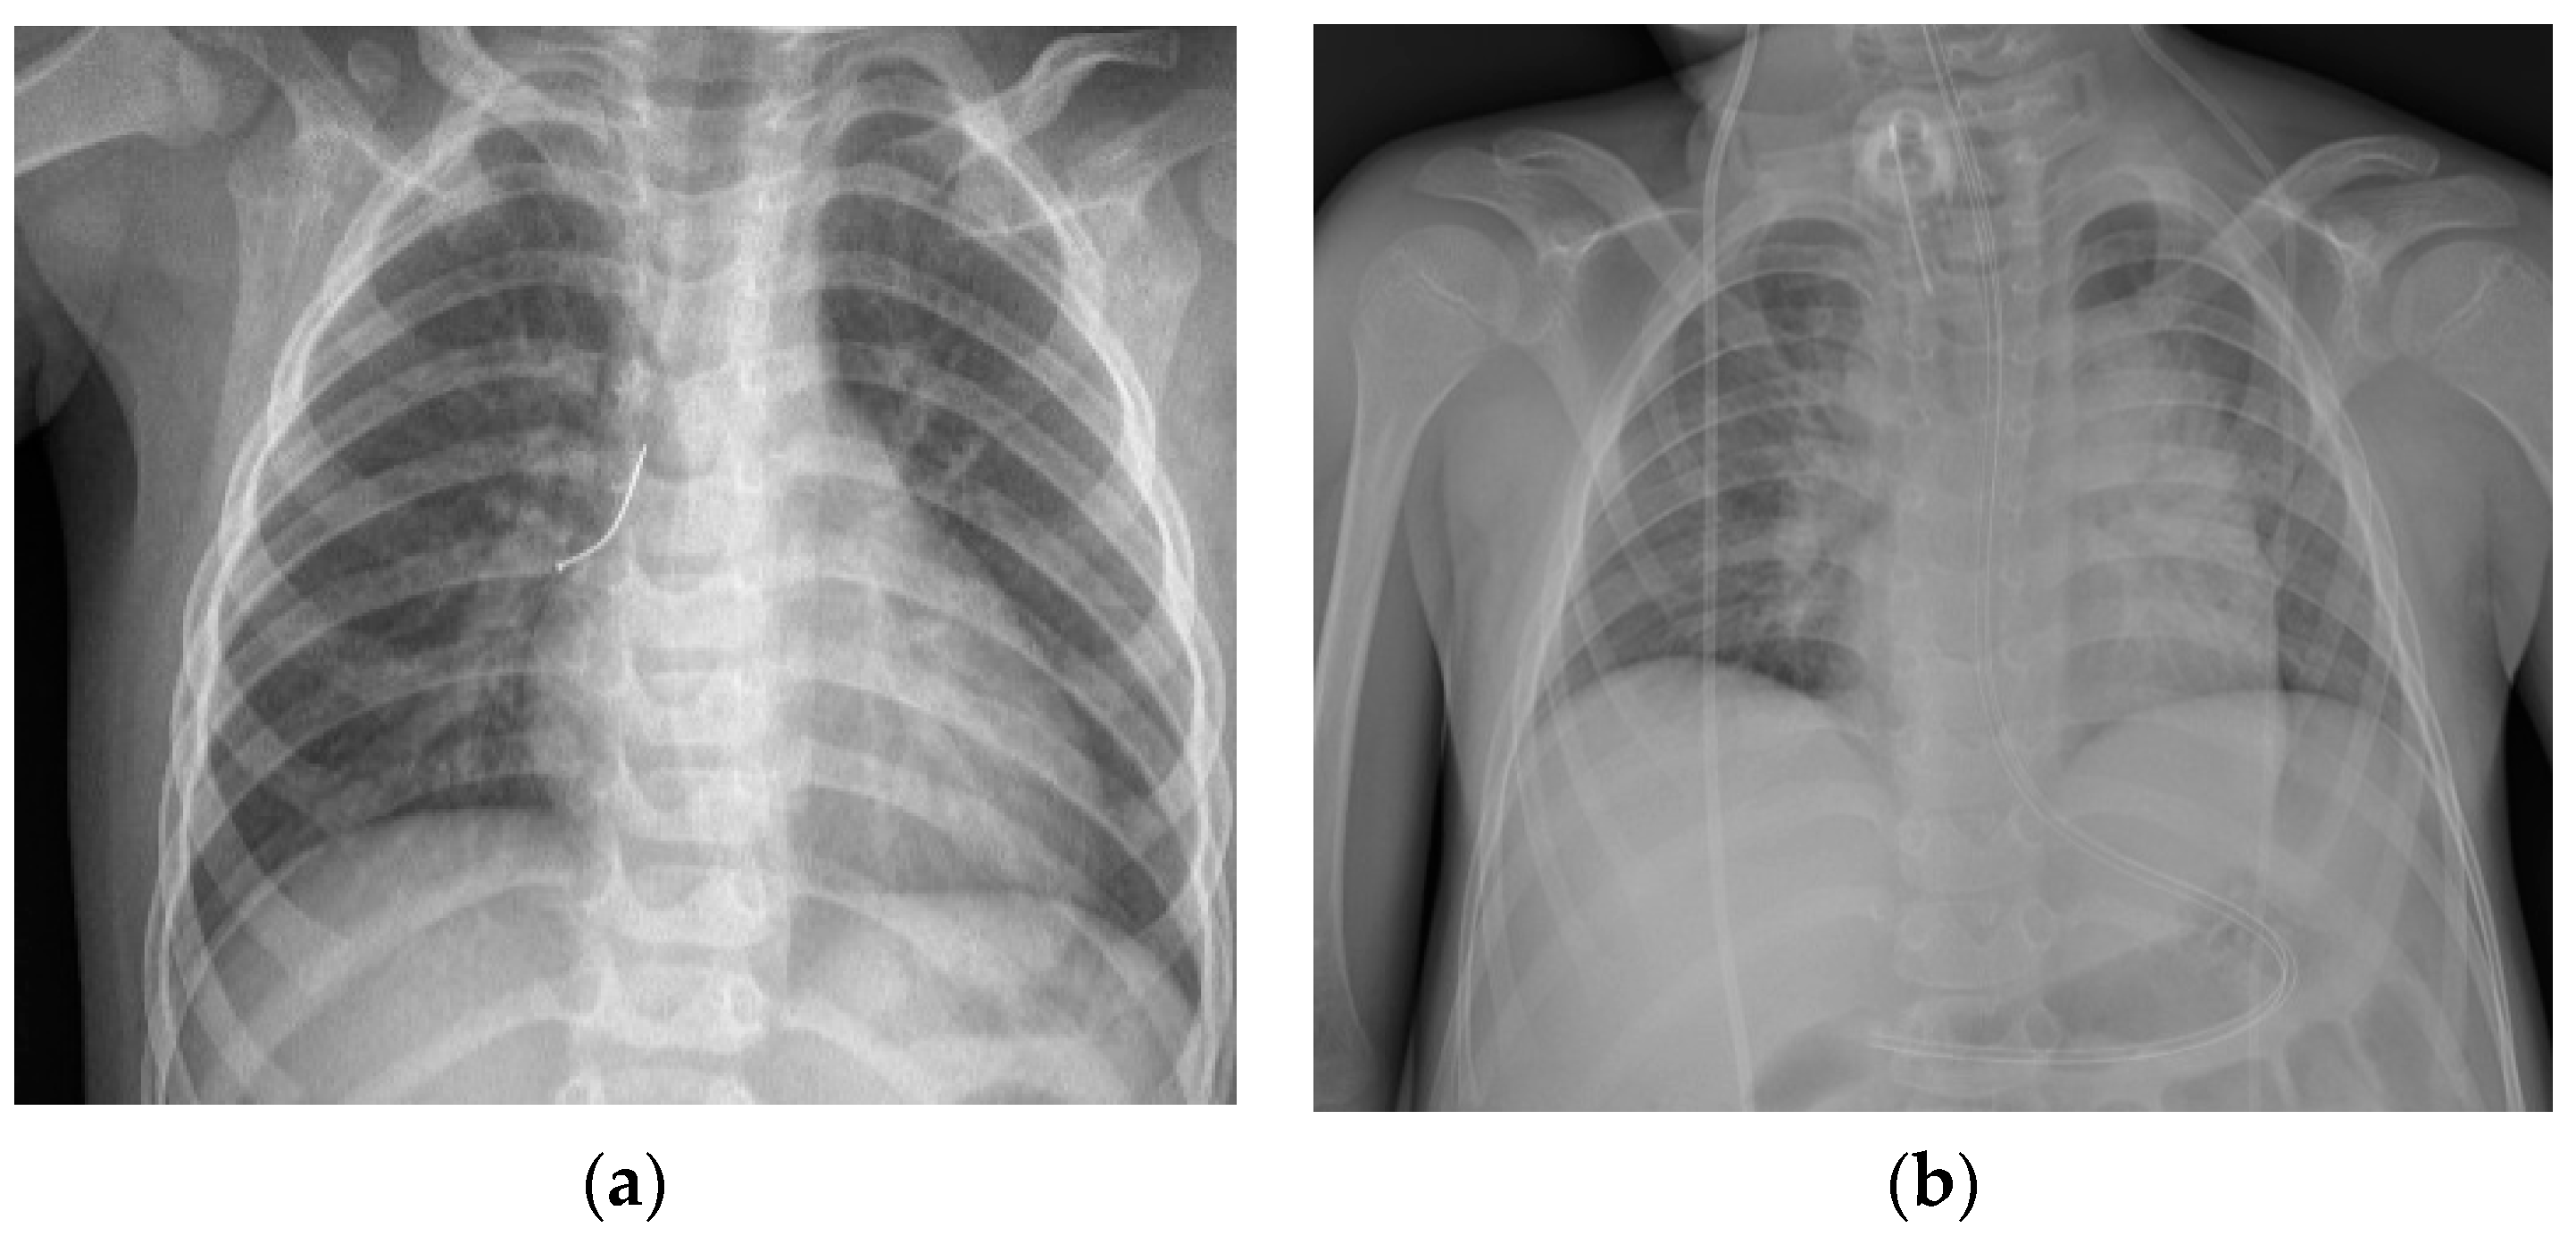

In the analyzed group, X-ray imaging results included: evidence of foreign body (metal objects), unilateral pneumothorax or atelectasis, intensified vascular pattern, emphysema, and mediastinum dislocation (Figure 3).

Figure 3.

X-ray imaging results. (a) Evidence of foreign body in right bronchi; (b) intensified vascular pattern; (c) mediastinum dislocation to right side; (d) mediastinum dislocation to left side.

When physical examination reveals dyspnea, cough, and excessive respiratory effort or fever, and chest X-ray image presumes a plausible foreign body aspiration, even if no choking episode was observed, it is recommended that rigid bronchoscopy be performed. Oversight and foreign body retention in lower airways may lead to serious adverse results [,]. Chest X-ray may show obvious evidence of foreign body (metal objects), but most times, radiologic image indirectly suggests the presence of an obstacle in the lower airways; in these cases, unilateral pneumothorax or atelectasis, emphysema, and mediastinum dislocation could be observed [,].